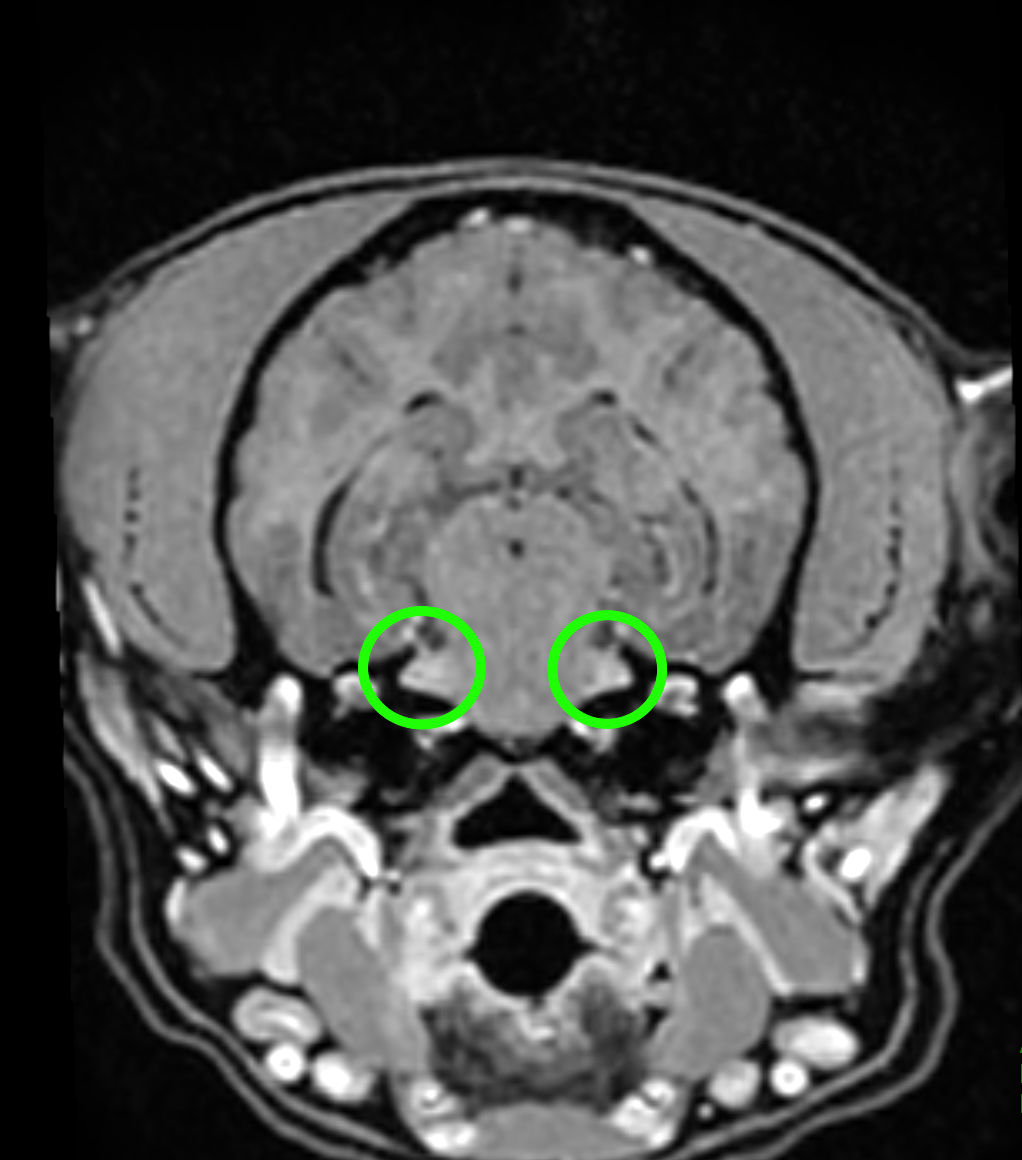

確定するにはMRI検査で三叉神経での炎症像を確認することが必要です

◯:三叉神経での炎症